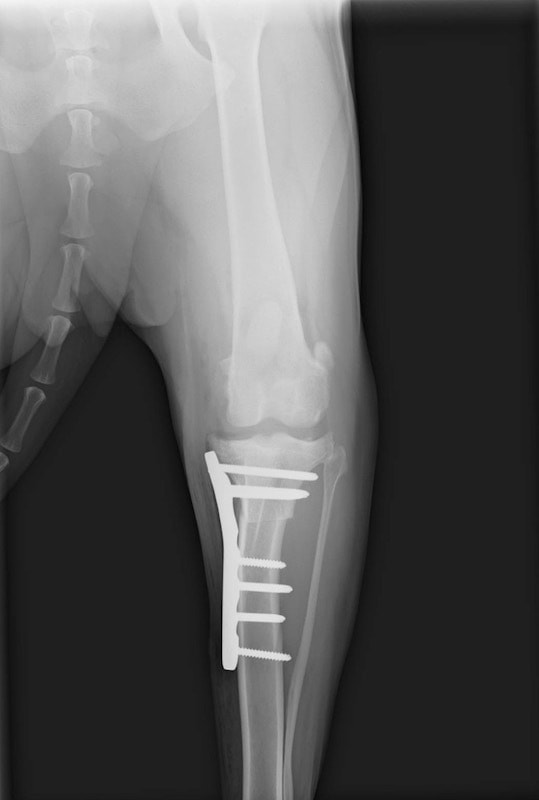

術後左後肢側面像

手術は片足ずつ行い、両膝とも術中の関節鏡検査にて前十字靭帯の完全断裂と半月板損傷を確認しました。TPLO、半月板切除と滑車溝形成を始めとした膝蓋骨脱臼整復術を実施いたしました。膝蓋骨の安定化を測るために外側支帯を強固に縫合し、内側支帯は切除し縫合せずに開放状態にしています。

術後の歩行状態は良好です。